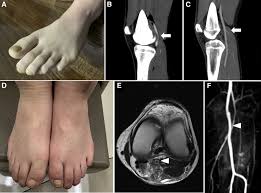

They later reported four more cases and claimed that the incidence of this pathology in patients younger than 30 years old with claudication was 40. Thrombolytic therapy can be used to treat acute and subacute occlusions of the popliteal artery due to underlying stenosis. Early diagnosis through a combined approach careful physical examination and history-taking duplex ultrasonography computerized tomography and angiography is necessary for exact diagnosis.

19 Year Old Female With Popliteal Artery Entrapment Syndrome Paes Download Scientific Diagram